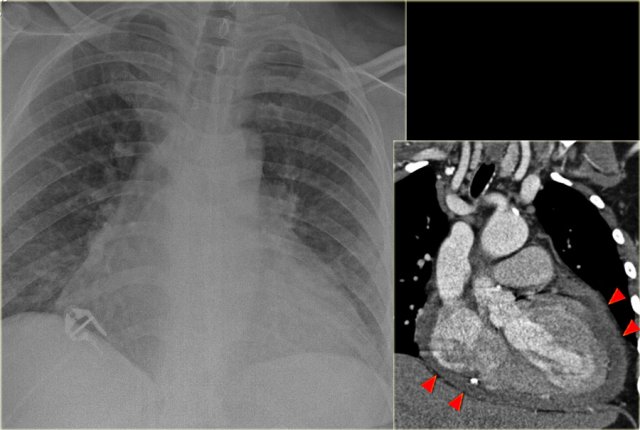

Increased CTR due to pericardial effusion Increased CTR due to pericardial effusion

On the left a patient, who recently underwent a valve replacement.

There is a large cardiac silhouette, which could be the result of cardiomegaly.

Because of the recent cardiac surgery, the possibility of pericardial effusion was taken into account, which is nicely demonstrated on the CT-image.

On the left another patient with a large cardiac silhouette on the chest x-ray due to pericardial effusion.

Pericardial effusion is demonstrated on the coronal CT-reconstruction.